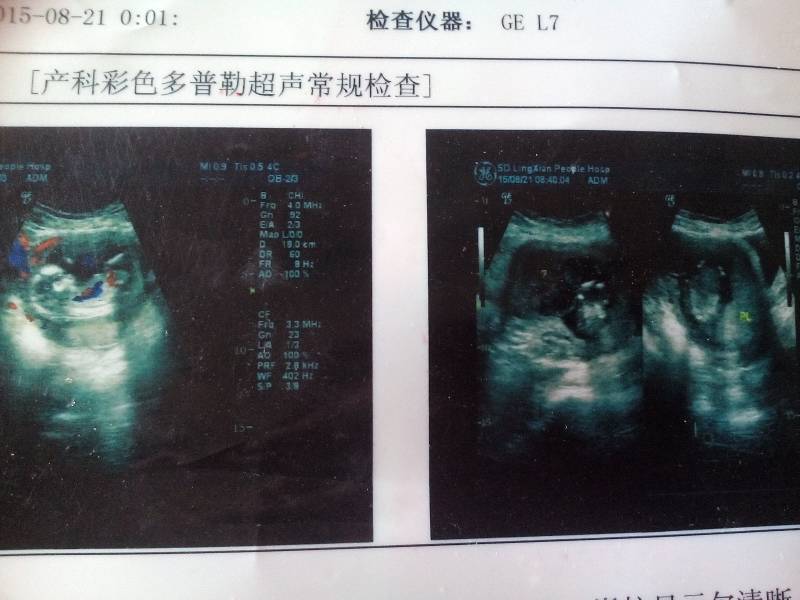

怀孕三个多月了,超声所见,胎儿可见颅骨光环,脑中线居中,双顶径约2.8cm,脊柱显示欠清晰,可见胎

怀孕三个多月了,超声所见,胎儿可见颅骨光环,脑中线居中,双顶径约2.8cm,脊柱显示欠清晰,可见胎心胎动,股骨长约1.3cm,胎盤位於左前壁,其下缘覆盖宫颈内口,实质回声均匀,羊水最大前後颈约3.0cm,内透声可,宫底处宫腔内可见范围约5.8#5.2cm低回声团块,内回声不均匀。轻问这是什麼意思啊,有看懂的帮忙看看,谢谢啦。